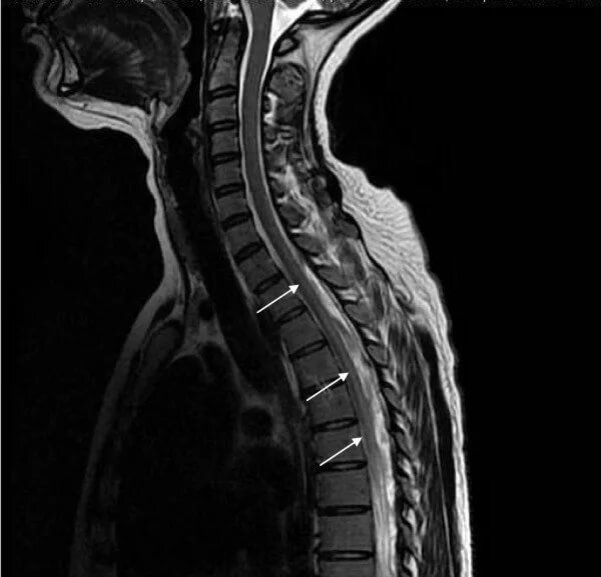

МРТ спинного мозга (она же МР-миелография) - это прицельное обследование спинного мозга и мозговых оболочек. Ее обычно проводят в медицинских центрах Санкт-Петербурга как дополнительный протокол сканирования в ходе МРТ позвоночника. Специальная программа миелографиии позволяет хорошо визуализировать спинной мозг и оценить ликвородинамику.

МРТ спинного мозга (она же МР-миелография) - это прицельное обследование спинного мозга и мозговых оболочек. Ее обычно проводят в медицинских центрах Санкт-Петербурга как дополнительный протокол сканирования в ходе МРТ позвоночника. Специальная программа миелографиии позволяет хорошо визуализировать спинной мозг и оценить ликвородинамику. Качественная МРТ спинного мозга потребует обследования на высокопольном томографе с мощностью магнита не менее 1,5 Тесла.

МРТ спинного мозга – это высокоинформативный метод исследования, который позволяет выявить любые патологии в спинном мозге даже на самых начальных этапах их развития. При подозрении на очаговые образования (опухоль, киста, демиелинизация) врач с высокой точностью сможет определить расположение очага, размеры, степень распространения, взаимоотношение с соседними тканями, а также провести дифференциальную диагностику между злокачественным и доброкачественным процессами. Также с помощью МРТ выявляются:

Большую роль МРТ играет и для диагностики демиелинизирующих заболеваний нервной системы, таких как рассеянный склероз, оптикомиелит или болезнь Девика, болезнь Марбурга, синдром Гийена-Барре. При РС с помощью томограмм хорошо обнаруживаются очаги демиелинизации, за которыми врачи наблюдают в течение некоторого времени и оценивают их количество и динамику роста. Для подтверждения диагноза рассеянный склероз МР-сканирование спинного мозга проводят несколько раз в комплексе с МРТ головного мозга.